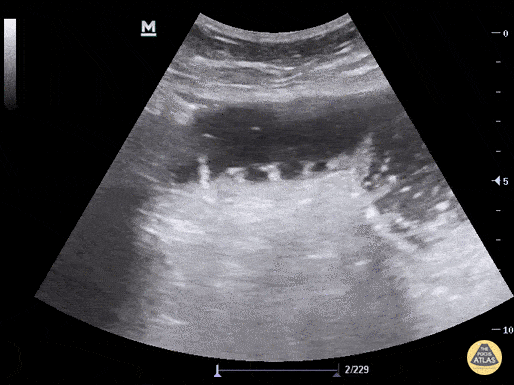

A patient presented to the emergency department with one day of constipation and abdominal distention. A bedside ultrasound was performed showing dilated bowel, to-and-fro peristalsis, and keyboard sign (plicae circulares). Low-grade SBO with transition point found on follow up CT. Aaron Inouye @PAintheED